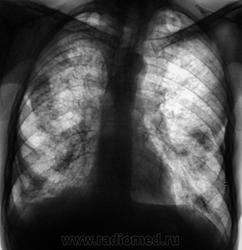

"От сегодня", вот такая "флюшка". Архива нет, почти БОМЖ

Гематогенная диссеминация tbc наверное

Сразу видно-БОМЖ.Но не туберкулёз,не похоже,диссеминация больше снизу,распадов больших нет.Канцероматоз?

Имеются полости распадов с обеих сторон,но вогру них не видно отсевов.Бомжи коварны,могут быть без туберкулёза.

Я тоже о лимфангите подумала сначала, как-то не совсем на туберкулез похоже.. но корни относительно структурны, и обять же... бомж)

Обдумав,могу сказать,что пока нельзя исключить туберкулёз на фоне чего-то более редкого и интересного.Уж больно рисунок лёгочный петлист.Справа в шестёрке-полость.Многое даст клиническое наблюдение и обследование.Интересны анамнез и клиеика.

Сегодня из "областной конторы" пришла информация. Выставлен диссеминированный, фаза инфильтрации и распада.

ВК+, СV+